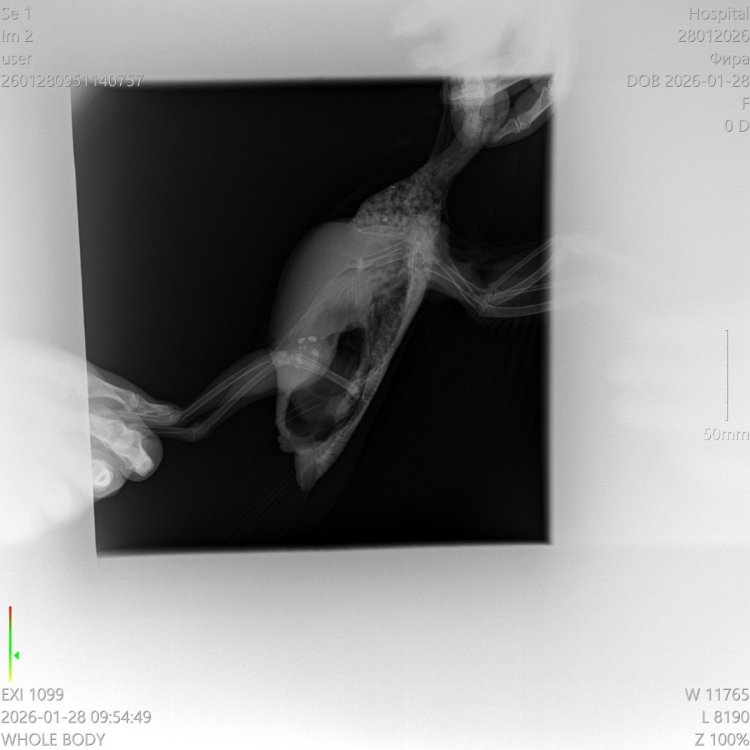

Сегодня сделади рентген. Сдали анализы, какие смогли: на кокцидий- отрицательно, на другие глисты - пока ждем, бакпосев помета и смыва с горла - будут говы или в конце этой неделе либо до следущей среды.

Ребят вот что Зося на рентген ответила «Перелом там есть, но малозначительный. Есть признаки воспаления надаостнмцы. Возможно разрушена суставная сумка. Надо принимать Целекоксиб, 10 мг на кг в сутки, 3 недели. Покой. Остеогенон и артрогликан 4 недели. Никаких полётов» Теперь вопрос в том, что принимать из того что дали в клиниках (и в каких дозах) чтобы это комбинировалось с назначением Зоси 😶🌫️ Зосе тоже не нравится назначение